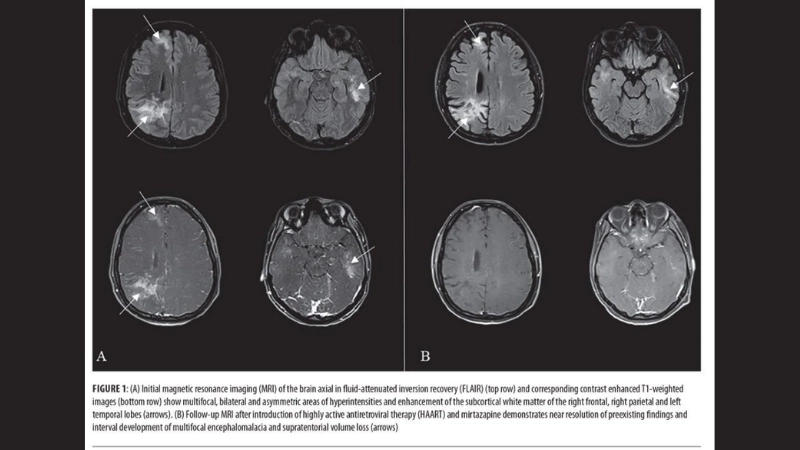

Progressive multifocal leukoencephalopathy cases show severe brain lesions